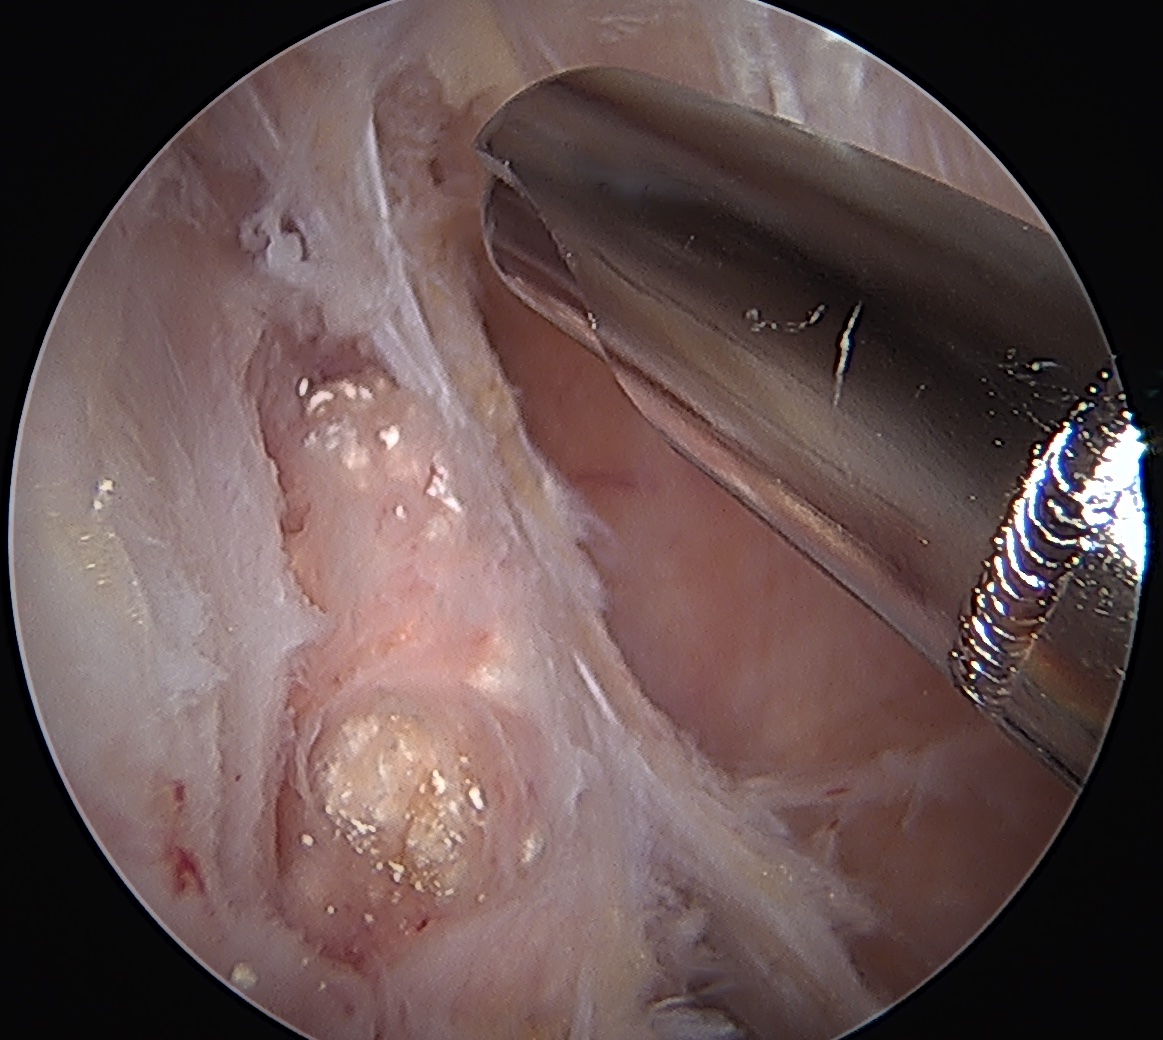

Arthroscopy